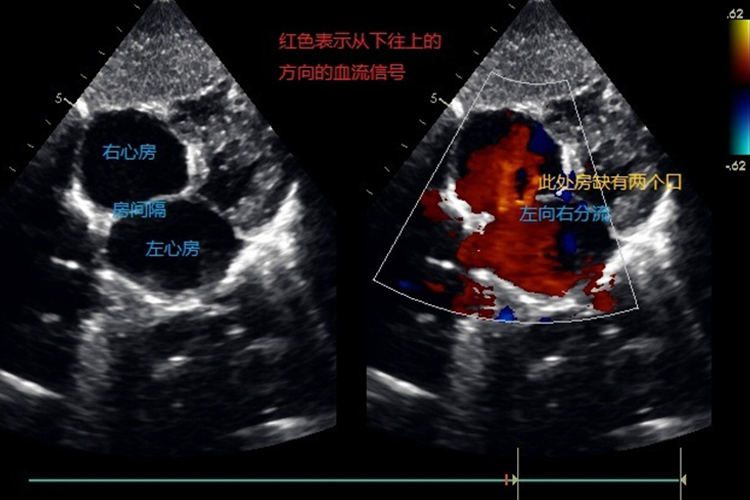

房间隔缺损彩超可见右心房、右心室的增大,还可见血流分流的频谱,可明确心脏并发畸形的位置。

房间隔缺损彩超可显示出房缺、右心房、右心室增大,肺动脉增宽。房间隔连续中断,并可见左向右血流分流频谱。